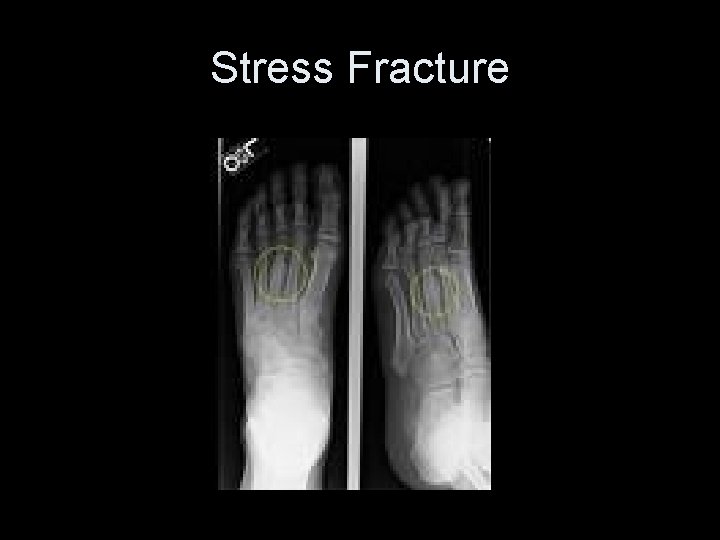

Stress Fracture 1. Results from an abnormal degree of repetition 2. Generally found where muscles attachments are 1. EX: runners at tib/fib 3. Not always seen on plain x-ray

Stress Fracture